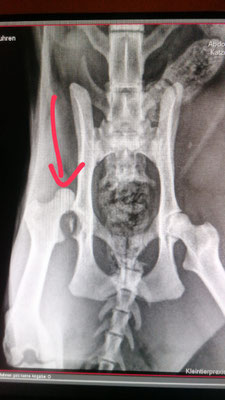

Rudi hatte 2024 vermutlich einen schweren Autounfall mit einem Hüftgelenksausbruch und einem Schwanzabriss. Normalerweise können Katzen mit einem Schwanzabriss von selbst keinen Urin / Kot mehr absetzen. Wie durch ein Wunder kann Rudi beides aber problemlos. Den Schwanz kann er allerdings nicht mehr einsetzen, er hängt also einfach locker nach unten. Rudi war anfangs sehr scheu, ein kleiner "Fauchi". Er hat sich aber sehr schnell an die Helferlein vom Katzenhaus gewöhnt und ist jetzt eine echte Schmusebacke.